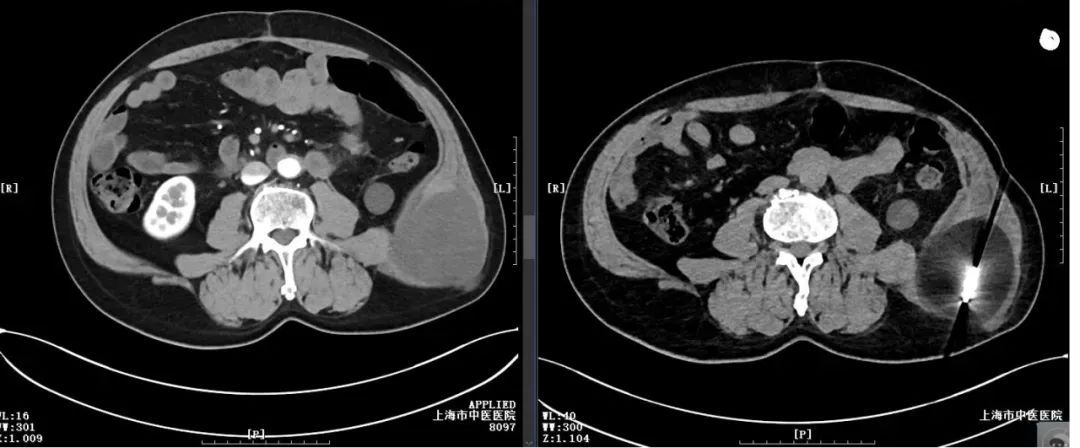

术前,根据影像所示肿瘤范围大小,共确定四个穿刺消融点。手术在镇静和局麻下进行,术中,王伟昱在CT的引导下,准确无误地将复合式冷热消融探针送达预定病灶位置。通过控制冷冻、复温循环,在术中CT监测下,产生的冰球不断增大直至冰球完全覆盖病灶。整个手术用时约70分钟,患者术中完全无痛感。

手术前后肿瘤对比(右图冰球已完全覆盖肿瘤)